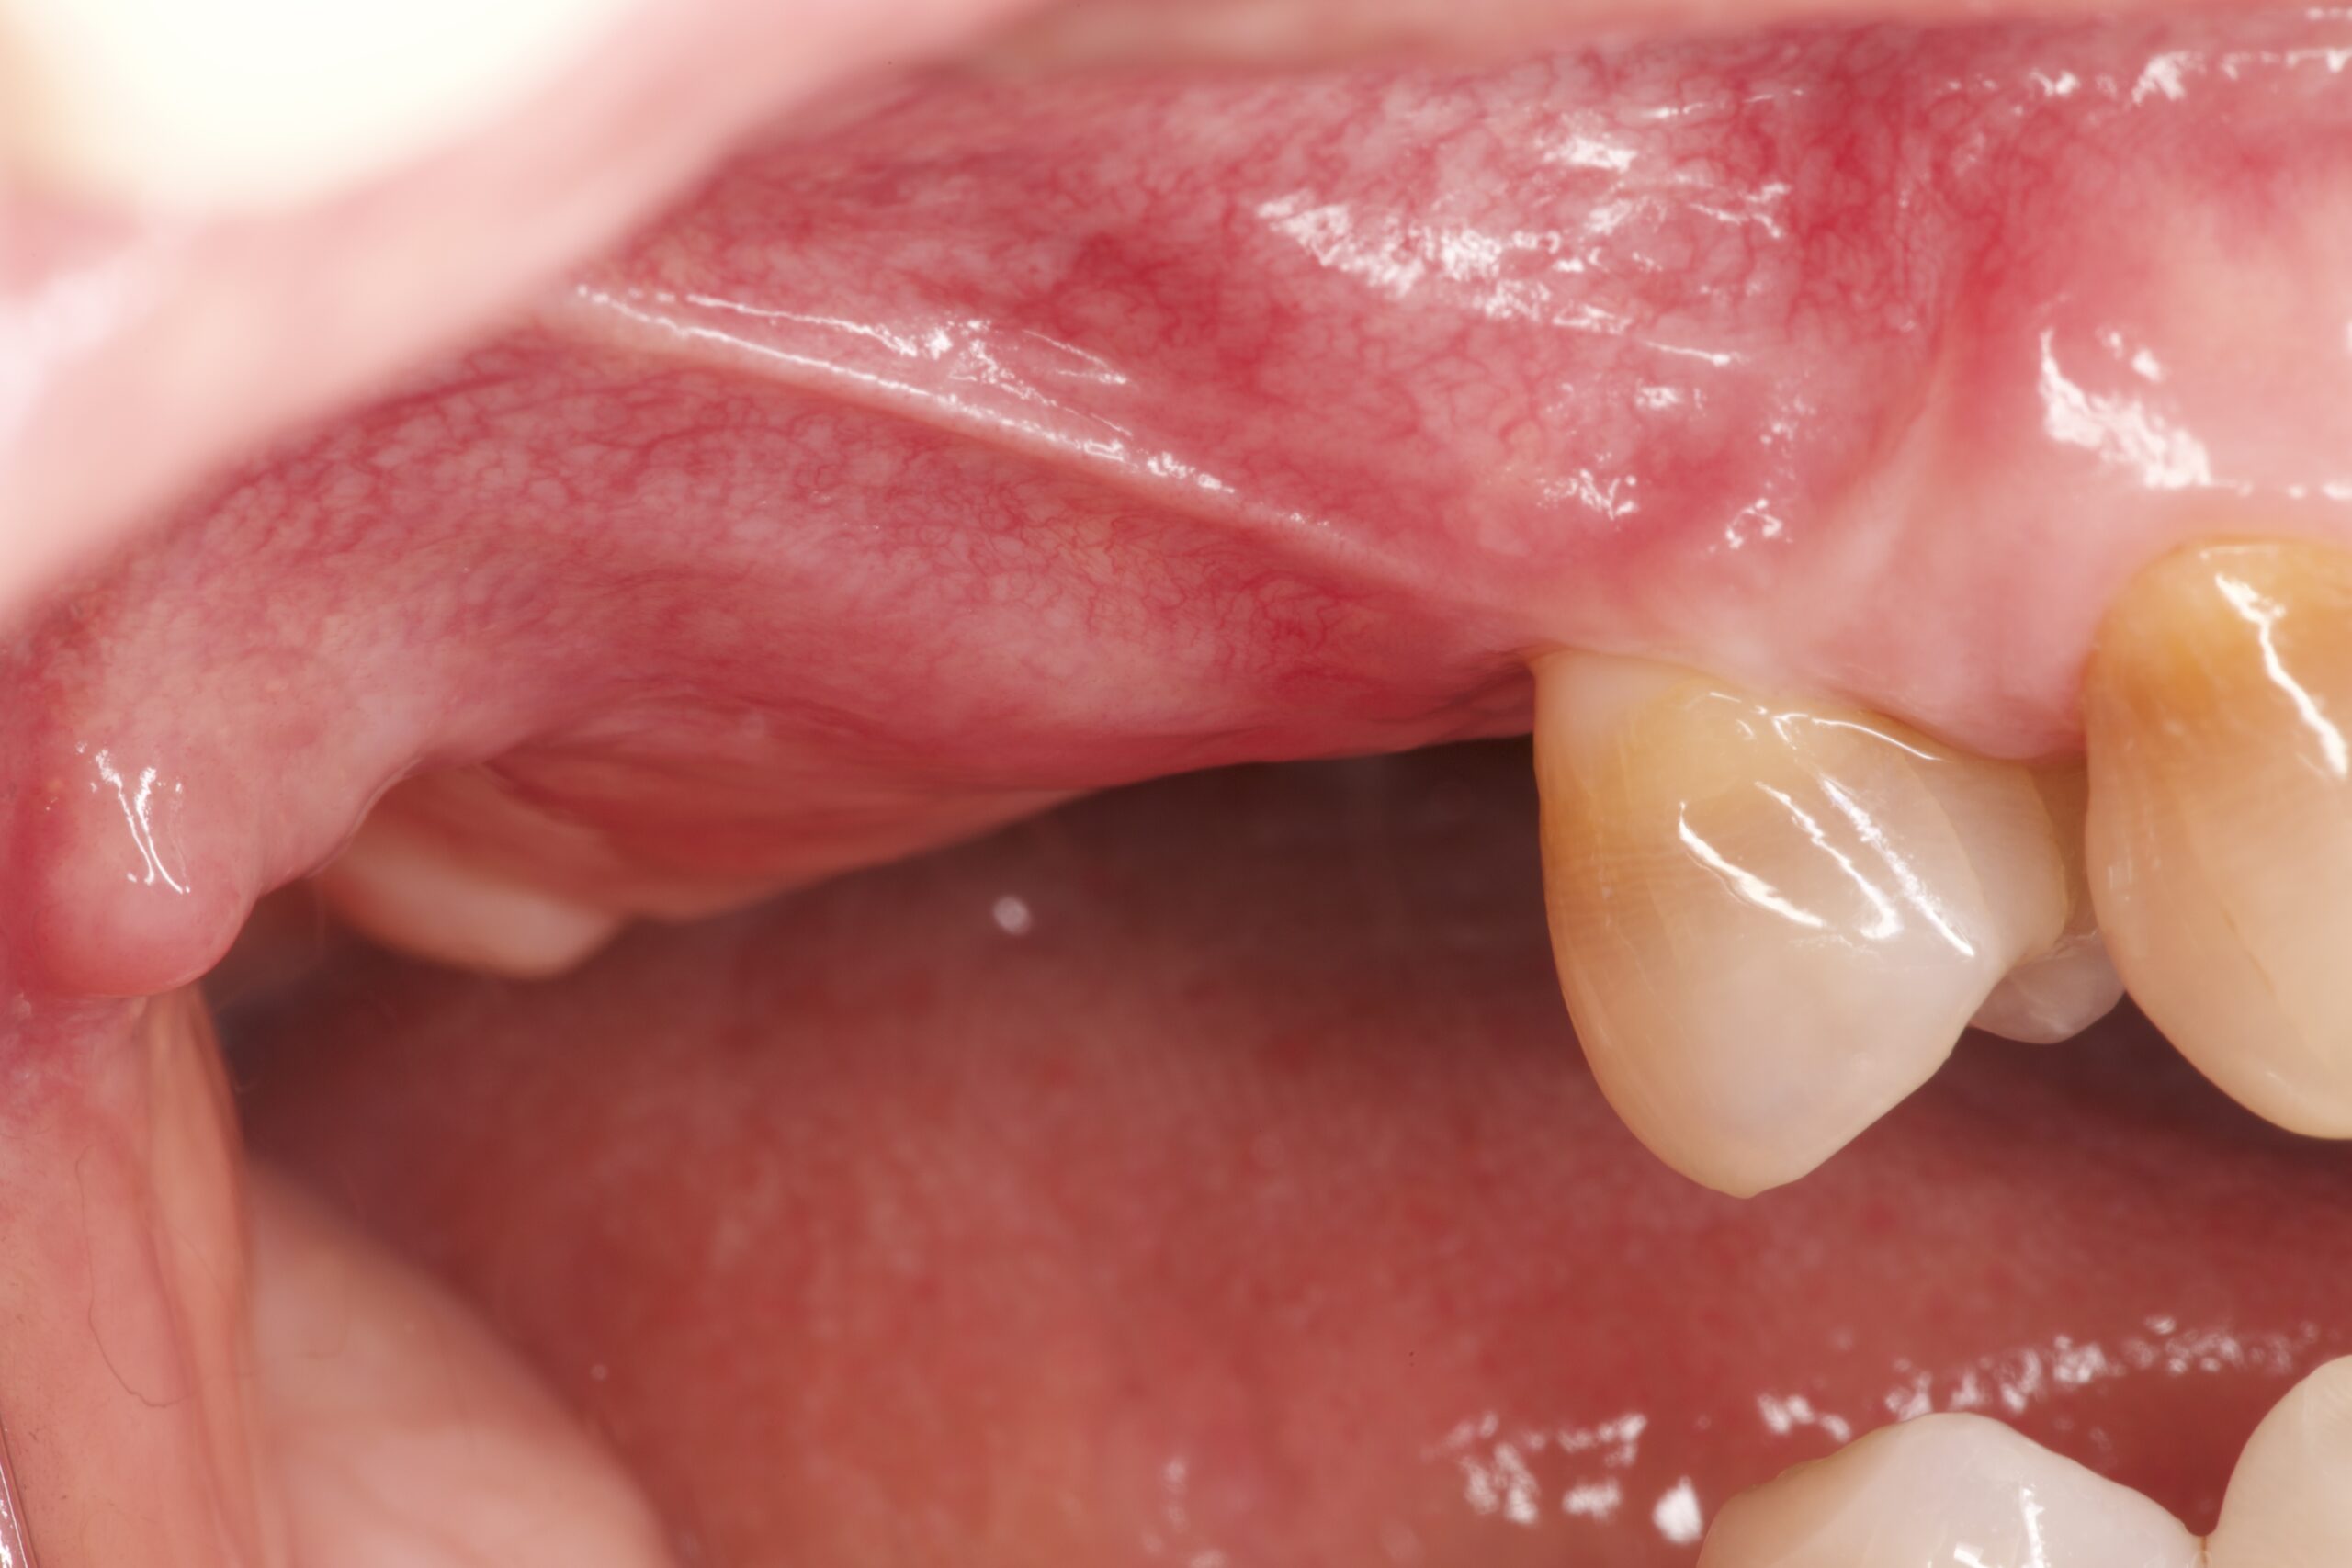

治療前

抜歯を行うと、さまざまな要因で元々あった骨は吸収してしまいます。インプラント治療が困難であるという説明を受ける際の原因の多くはこのためです。